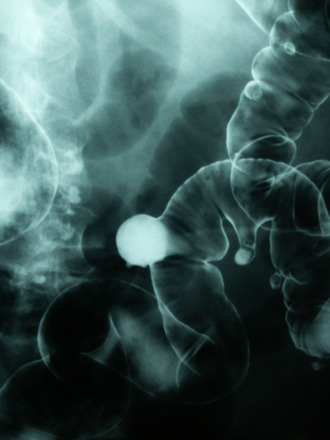

Rys. 1